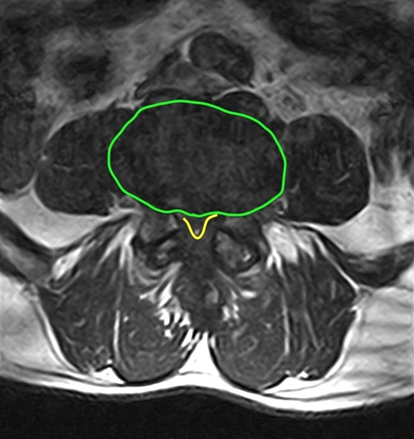

Hình 1. Hẹp ống sống L4-5 trên phim MRI chuỗi xung T2 mặt cắt dọc và ngang: Lồi đĩa đệm(màu xanh) và phì đại dây chằng vàng (vàng) (nguồn: radiopaedia.org.